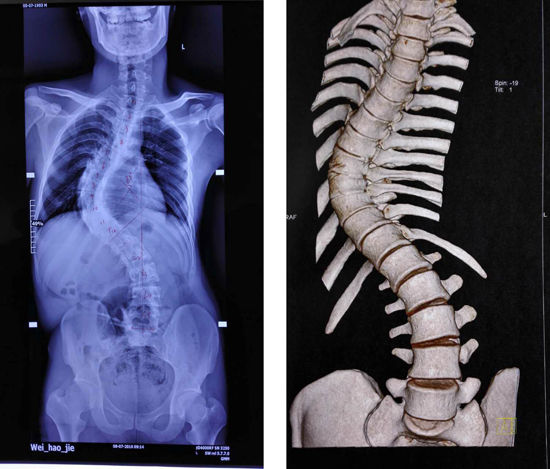

在入院后,医生对小魏进行了详细的检查:躯干向左侧倾斜,右肩比左肩高2cm,脊柱右侧凸,右侧“剃刀背”畸形,高约4cm,右侧锥旁肋骨隆起畸形,站立身高157cm。拍片结果显示:下胸椎多节分节不全,侧弯Cobb角高达82°,且为椎体分解不良,僵硬型脊柱侧弯。

一周后,小魏已经能在支局保护下顺利下床活动,拍片显示脊柱得到良好矫正,身高达到了171cm,较术前高出约13cm,脊柱侧弯角度减小至23°,外观改善后基本看不出来,心肺功能逐渐接近正常。